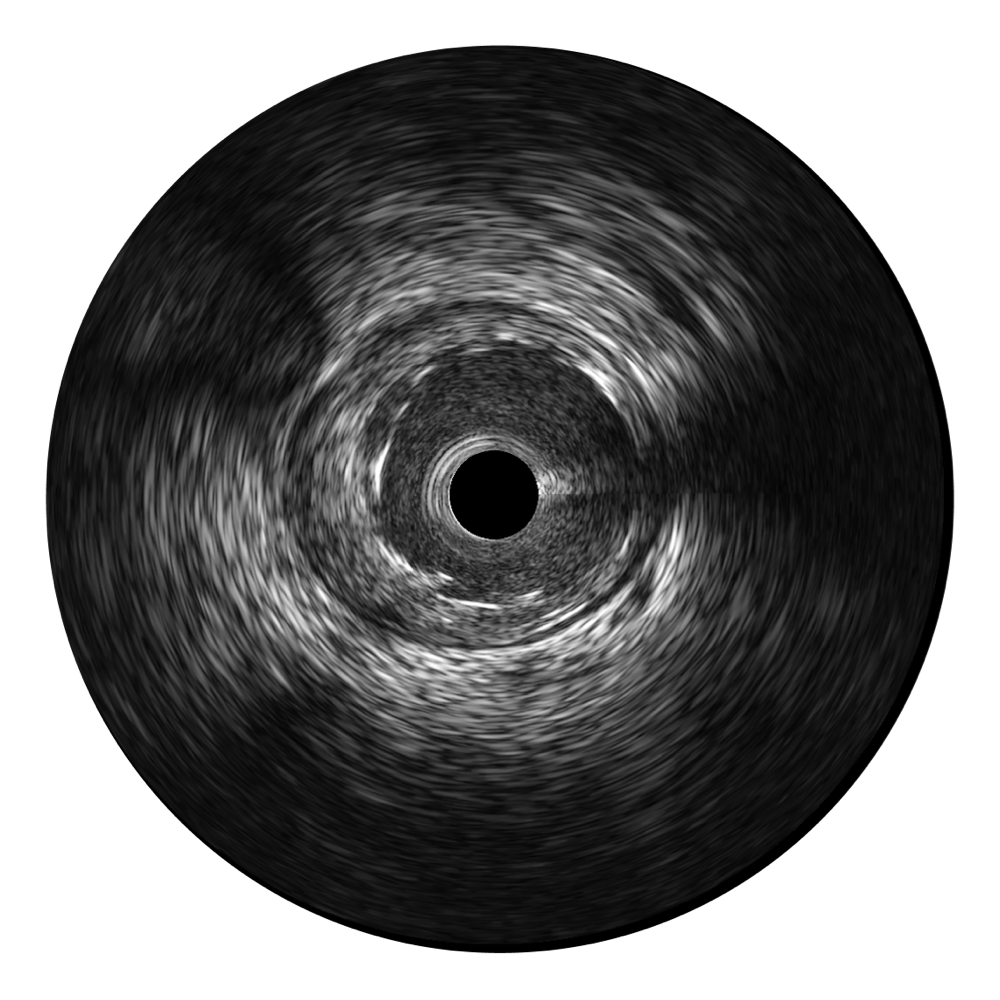

狗万官方网站宽频IVUS图像

对比传统IVUS导管成像,狗万官方网站宽频IVUS图像的近场支架梁显影更细腻,远场中膜外血管仍清晰可辨,兼顾远中近,兼顾分辨力与穿透深度